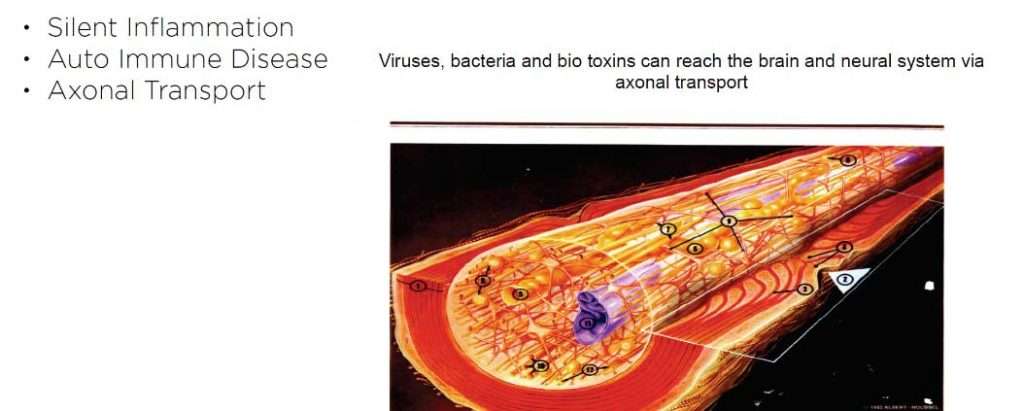

The problem with root canal therapy is it is a flawed therapy, the intention behind doing it is to be able to fully sterilize a tooth which no longer revives blood supply, nerve supply, lymph drainage or any signs of so called life. Anything that is non-vital is usually energetically a break in the circuit. This is the reason why people who have multiple root canal treated teeth complain of chronic fatigue, insomnia as some of the presenting symptom. Any non-vital part of the body is the breeding ground for gram negative anaerobic bacteria and the toxins from this low grade chronic inflammation(silent inflammation) activates the immune system. People with multiple root canal treated teeth usually present with some form of autoimmune condition on their health history.

The problem with root canal therapy is it is a flawed therapy, the intention behind doing it is to be able to fully sterilize a tooth which no longer revives blood supply, nerve supply, lymph drainage or any signs of so called life. Anything that is non-vital is usually energetically a break in the circuit. This is the reason why people who have multiple root canal treated teeth complain of chronic fatigue, insomnia as some of the presenting symptom. Any non-vital part of the body is the breeding ground for gram negative anaerobic bacteria and the toxins from this low grade chronic inflammation(silent inflammation) activates the immune system. People with multiple root canal treated teeth usually present with some form of autoimmune condition on their health history.

Activation of T cells which are a part of our immune system in systemic inflammatory processes (like- Cancer, Heart disease, Arthritis(substance P), autoimmune diseases, neurodegenearative diseases like parkinsons, and Alzhiemers disease) causing elevated levels of Interleukin-6 (IL-6) and chemokine ligand 5 (CCL5), also known as RANTES (regulated on activation, normal T cell expressed and secreted). Higher the RANTES Score higher the incidence of chronic oxidative stress related diseases.

Silent inflammation due to root canal therapy, cavitation (avascular osteonecrosis) and titanium implants leads to immune system activation. The intraoral interference fields created by metals, NICOs, bacteria in root canal treated teeth produce highly toxic hydrogen sulfides (Thioether/Mercaptan), metals show cytotoxic, immunological and carcinogenic effects and NICOs (Neuralgia inducing osteonecrosis) consist of increased inflammatory mediators like RANTES, FGF-2 and IL-1ra.